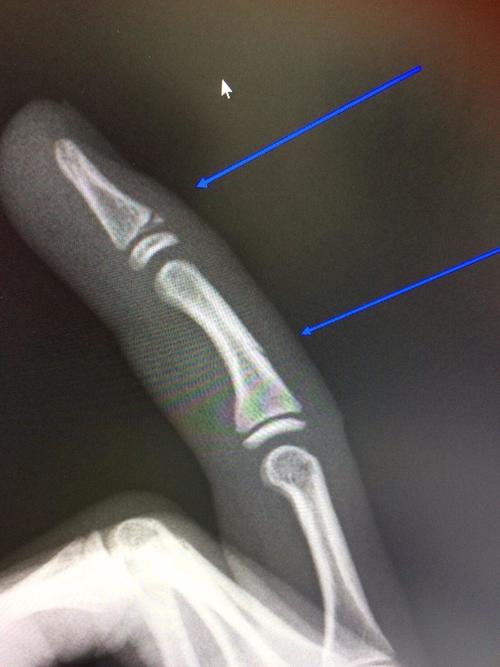

初診時、右中指の中央~末端部に腫れと内出血を確認し、指を曲げれない状態。

結果、中指の中節骨部に亀裂、末節骨骨端軟骨部にも異常を確認。。。

最終結果は「中節骨骨折」及び「末節骨骨端軟骨骨折(ソルターハリスⅡ型)」

お子さんの骨は、骨の端に骨端軟骨という、骨が伸びる場所があります。

この骨端軟骨部(成長線)が傷ついたりすると、成長障害を起こす場合があり注意が必要です。